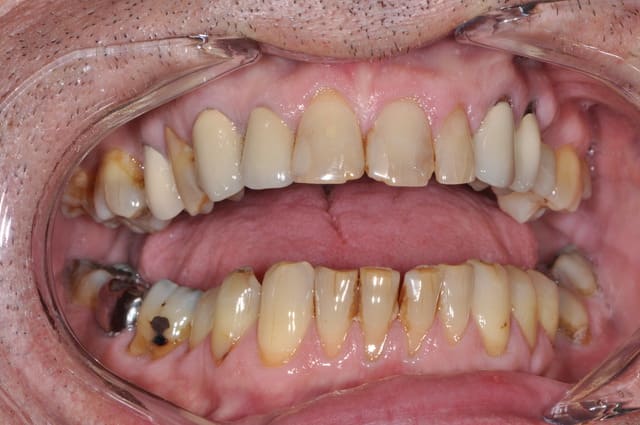

OK on y voit plus clair, si on prend l'image comme une référence, ce qui me choc autant que le bloc antérieur d'un point de vue esthétique (et là encore c'est une vision subjective donc à faire valider au patient d'abord), c'est la position de 14, 15 ,16, ingressées suite à affaissement occlusal, oui je sais c'est fonctionnel, mais c'est moche aussi!!!!

Ensuite sérieusement les CCM en place font toc, c'est aussi moche, encore une fois ce contenter de 12 à 22 me semble léger, même si dans le shèma du sourire "vrai" l'esthétique de la gencive est tout d'un coup devenue secondaire.

Alors ce battre pour savoir si on fait des couronnes ceramoceram ou des 3/4 ou des facettes, alors que le reste ne ressemble à rien, n'a plus trop de sens non?

Pas du tout d'accord : je suis même choqué de ces réponses. Le patient se fiche de ses dents du bas et s'intéresse aux incisives sup. Ne pas restaurer les dents du bas n'a strictement aucune importance sur le plan médical, donc pourquoi en rajouter.

Pour les 3 antérieures, je proposerais 3 couronnes in céram ou e max. Il faut voir ce que les patients demandent et pas devenir un obsédé compulsif de la perfection.

la réalisation d'un traitement global prothétique ou d'ortho se tient au regard de l'affaissement occlusal du bloc postérieur, l'occlusion plus ou moins foireuse de ton patient risque de le placer devant un pronostic esthétique moyen à long terme, c'est déja le cas au niveau 23 et 24, donc se contenter de 12 à 22 me parait léger. Mais bon le terme esthétique est tellement floue!